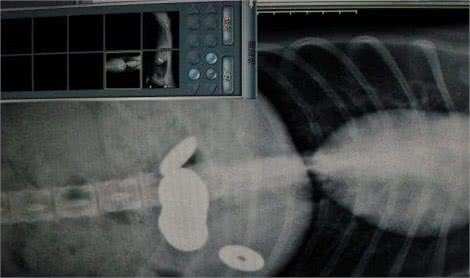

医生给哈士奇检查了胃,拍摄完X光片的时候却看傻了,这家伙居然一肚子都是钱,还都是铜钱!这些铜钱的数量还挺多的,有的分布在胃部底部,有的卡在胃和肠道的地方,这也是哈士奇为什么不想吃东西的原因,因为胃部被卡住了!

医生只好赶紧进行手术,把这些铜钱全部取出来,以防止哈士奇出现更严重的问题,全部取出来的时候,居然一共有14枚铜钱,而且这些铜钱的个头还都不小,所以卡住自然而然的事情了!